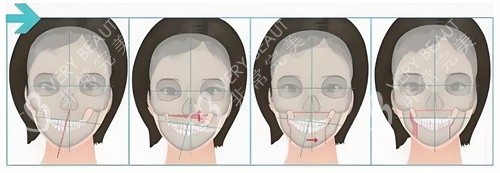

医院拥有韩国头一个"智能化轮廓模拟中心",可通过3D打印技术制作患者专属骨骼模型进行术前演练。

医院采用CT导航辅助系统更好定位,配合自体脂肪移植调整面部平衡。

导航辅助截骨系统:实时影像引导确保截骨精度达0.1mm级

动态平衡评估:术后进行为期6个月的面部肌肉功能训练指导